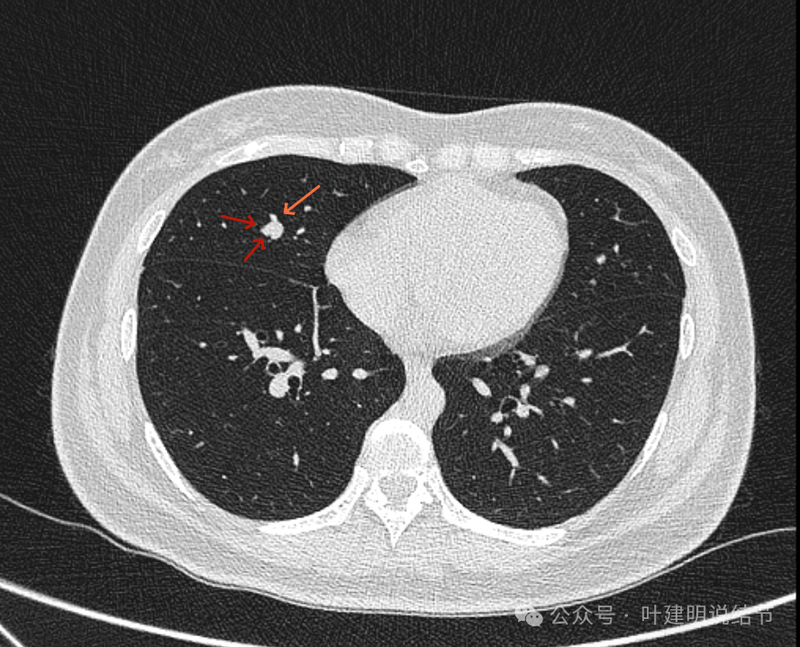

病灶出现,图上标注的桔色箭头所指的是肺血管;红色箭头所指的是病灶;天蓝色细线指的是血管与结节之间的间隙。病灶实性,与血管挨得近,但没有紧贴或侵犯。

病灶与血管间仍有低密度线状,血管在此处刚好分叉似的。

病灶有膨胀性,血管贴得近。

似乎见血管围着结节灶,两者紧贴,密度略有不同,导致上图中血管受压成细条状,病灶是软组织密度。

看着像靠心脏这一侧的半圈是血管受压形成的包膜似的,但靠胸肋侧没有血管,所以略偏白些的血管影在外侧见不见,外侧见到的是病灶的边缘,比较光滑,两者之间密度不同(天蓝色细线所指是两者分界,虽紧挨却密度不同)。

上图也示病灶与血管的关系。

上图像病灶位于中央,周围有三支不同血管围着它。

确实是三支血管围着病灶,中间的是结节,另三处均是血管。